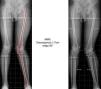

Caso #1Paciente femenino de 14años de edad, sin antecedentes patológicos de importancia. Refiere que hace 2años tuvo un trauma en la rodilla derecha, luego del cual la rodilla se fue desviando hacia afuera progresivamente, por lo que actualmente consulta por dolor, bloqueo en rodilla derecha y cojera para la marcha. Se solicitan estudios radiológicos con la finalidad de descartar alguna lesión osea (fig. 1).

Por el bloqueo que presentaba la paciente en la rodilla se solicitó resonancia magnética en la rodilla afecta, que no reportó lesión ni en meniscos ni en ligamentos (fig. 2). Se complementa con estudios de imagen por la discrepancia en la longitud de las extremidades inferiores, que aparentemente es de 2cm, por lo que se solicitó telemetría radiográfica de miembros inferiores para determinar la discrepancia exacta (fig. 3).